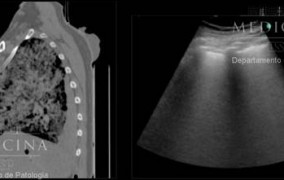

Es un tomógrafo desarrollado por una empresa brasileña, que ayuda a los médicos de un hospital de la Universidad Harvard a implementar estrategias de ventilación mecánica individualizadas y a disminuir la necesidad de la terapia de oxigenación con membrana extracorpórea con pacientes graves